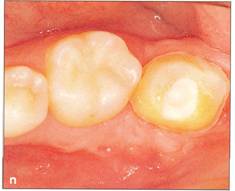

Fi 545e45f g 5-11 Preparation of the recipient site with surgical round burs. Fi 545e45f g 5-1 m Prepared recipient site and extraction site of the donor tooth. Fi 545e45f g 5-1 n After transplantation of the donor tooth and suturing of the flap. |

Fi 545e45f g 5-10 Stabilization of the donor tooth. The donor tooth has been splinted to the adjacent tooth with twisted wire and selfcured composite resin after etching and bonding. Fi 545e45f g 5-1 p After transplantation. |

Fi 545e45f g 5-15 Three weeks after transplantation. Root canal therapy was started 2 weeks after transplantation. After temporary obturation with calcium hydroxide, the root canal was obturated with gutta percha in 5 weeks. Fi 545e45f g 5-1t Two and one half months after transplantation. |

Fi 545e45f g 5-1 u Definitive occlusal restoration of the donor tooth with composite resin. Fi 545e45f g 5-1v One year 3 months after transplantation. Normal periodontal ligament space and lamina dura are observed. |